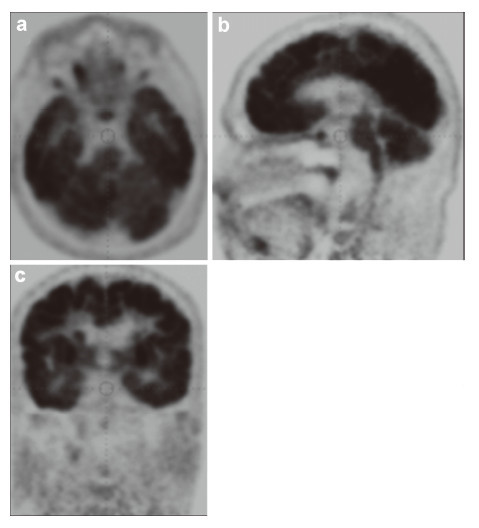

The data of the analysis of metabolic changes in different areas of the brain/spinal cord can be received from PET. Fusion of the PET images with the CT permits accurate coupling of the evidence of metabolomic disorder in the site of injury and its localization in organs and tissues. Therefore,the technology of the fused PET/CT opens new perspectives in the diagnostics of morphofunctional changes and their location in the anatomical formation of the brain. We can receive the data about magnetization of NT as a functional characteristic of the NT damage using magneto-encephalography (MEG). The data of threedimensional mapping of EEG provide us the evidence of the location of bioelectric activity of the brain cortex.

Program fusion of these data in the tables of bio information mapping of the brain with the data of MRI and CT gives us integral characteristic and maximally verified biological information of the personalized data that can be used by contemporary IT‐technologies and methods of mathematical modeling. Hence,these contemporary data of the imaging of the human brain help plan our restorative efforts in the neuroengineering, determine the main directions and information levels of the reconstruction of the brain and spinal cord and to evaluate the scope of requisite biomaterials and instruments. The specialized software for multilevel fusion (multi‐fusion) of the data of MRI,CT,PET,EEG mapping and MEG will produce a table of the parameters of different brain areas,so that it is possible to compare it with the table of the norm and to detect the injuries and functional disorders that have been missed by the physician during the visual analysis.